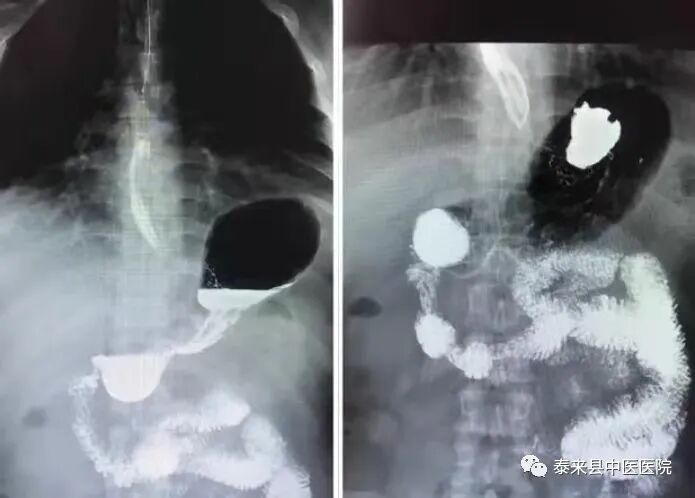

数字化胃肠透视检查以其痛苦微小、快捷安全的优点,对功能性、器质性病变(吞咽功能障碍,贲门失弛缓症,胃下垂,粘膜脱垂等)进行动态实时观察、整体与局部相结合的方法,有效的减少了内镜及CT、MR检查盲区,对术后复查及常规筛查的患者提供了更多的诊断依据。

2、数字化造影

将密度和组织器官有差异的造影剂导入人体检查部位,并检查组织器官是否存在病变。通过动态摄影观察组织器官的功能运行情况,并实时点片摄影。适用于食管、上消化道、全消化道等普通造影及静脉胆道造影、T管造影、静脉肾盂造影、逆行肾盂造影、子宮输卵管造影、膀胱造影、脊髓造影等普通及特殊造影。